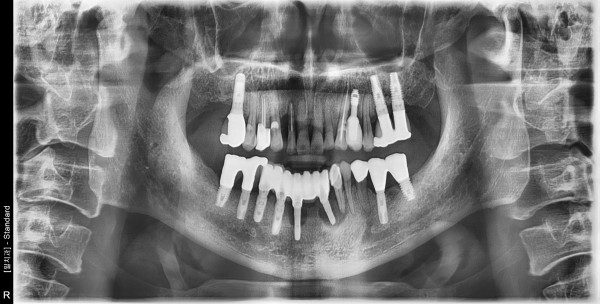

62세 남자환자/ 하악전치부 임플란트실패 제거후 재식립